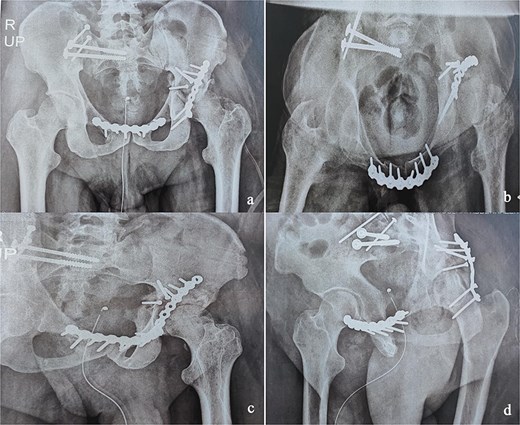

At the 10-month follow-up, the patient showed signs of left hip osteoarthritis with functional deterioration, for which a total ceramic-on-ceramic hip arthroplasty was performed, using a screw-fixed structural graft at the acetabulum (Fig. 3). At the final follow-up, 36 months postoperatively, the patient was walking unaided with the use of an anti-equinus splint on the left foot. The HHS was 85 and Majeed score was 86 [6, 7]. X-rays showed complete bone healing of all fractures and the acetabular graft. It should be noted that, during follow-up, the patient had a right femoral fracture that was successfully treated with a gamma nail (Fig. 4). Written informed consent were obtained from the patient.

Immediate postoperative X-rays. (a) Anteroposterior pelvic X-ray. (b) Inlet view of the pelvis. (c) Alar oblique view of the pelvis. (d) Obturator oblique view of the pelvis.